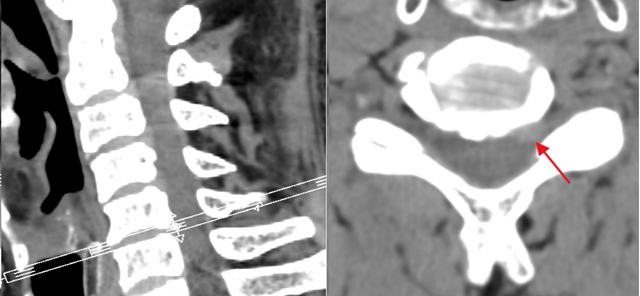

70岁的蒋先生1周前突然出现左上肢放射性疼痛,从颈部一直延伸到上臂,伴有麻木、无力感,于当地医院针灸没有改善后,来到骨伤科·脊柱骨肿瘤一组就诊。经戚力升主治医师详细检查,结合影像学检查,诊断为颈椎5/6节段椎间盘突出,突出的髓核压迫神经根,导致左上肢神经症状。

术前

术后